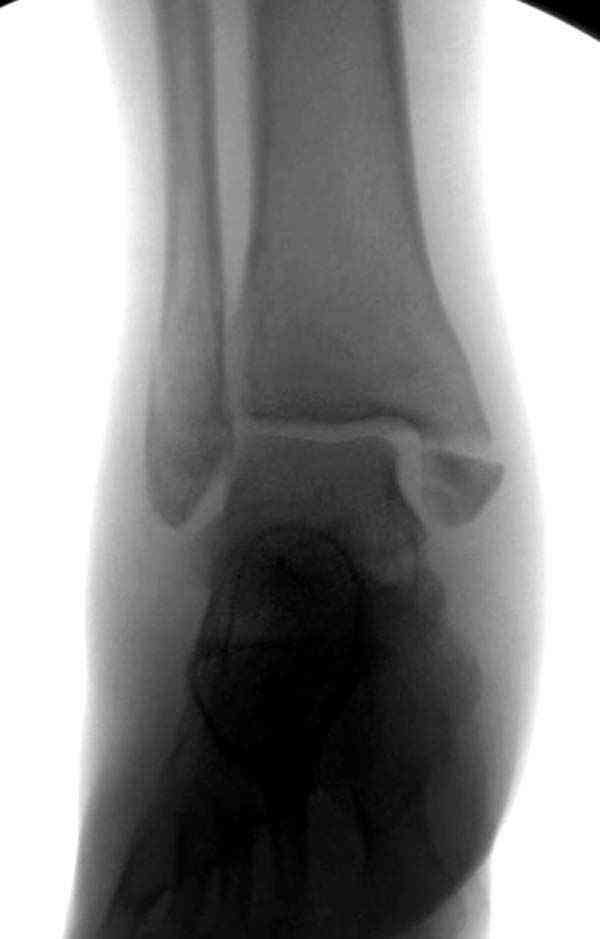

Раз ,есть желание посмотреть другую проекцию выкладываю-ну лучшего качества нет...

Достаточно быстрое восстановление функции.В октябре 2009г-почувствовала боль,в области рубца над гайкой открылся свищ.На Р-граммах-консолидация переломов и смещение гайки по стяжке.10.11.2009г-конструкции удалены,санация,заживление ран.В настоящее время пациентку ничего не беспокоит.На операции-раскручивание гайки-болталась на конце стяжки.Вопросы:какой механизм раскручивания и что я неправильно сделал?Свои версии:1)в области синдесмоза успела образоваться рубцовая ткань,которая при движении в суставе"пружинила",поскольку голеностопный сустав является спиральным, то и биомеханика подобна кривошипному механизму.2)Реконструктивная пластина не "реконструировалась" по форме лодыжки.Наложил,как есть.То есть подпружинивала сама пластина.Ну,это мои догадки.Что нужно,чтобы избегать впредь таких,пусть и не "страшных"осложнений:Рассверливать через лодыжку область синдесмоза?Ставить шайбу-гровер?Тщательно моделировать пластину?Прилагаю сравнительные снимки-сразу после операции и перед удалением конструкции.

Добрый вечер, коллеги! Хотелось бы увидеть стандартные проекции, прямо, боком и мортиз. Дело скорее всего не в пластине. Стяжка скорее всего не дотянута изначально. Отсюда игра синдесмоза и прорезывание проволоки Вебера. Вообще то стоило бы делать по классике , а именно : Наружная лодыдка - противоскользящая плата по Веберу, над синдесмозом - два позиционных винта ( это "ключи" сустава) внутренняя лодыжка - можно и проволокой, но при адекватной фиксации латерального комплекса.